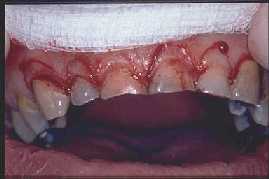

GINGIVECTOMIA

SE RETIRA ENCIA SOBRANTE